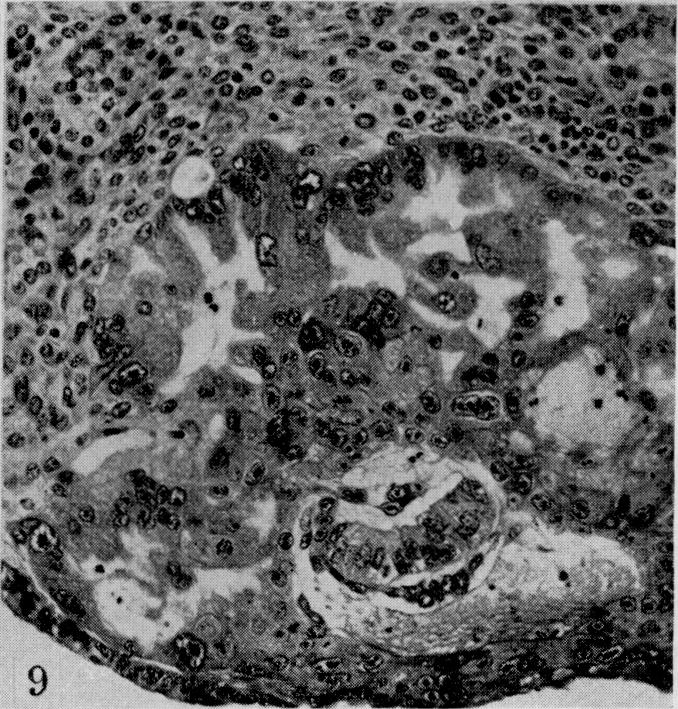

On the development of the amnion and exoccelomic membrane in the previllous human ovum.

Yale J Biol Med. 1945 Dec;18(2):107-15.